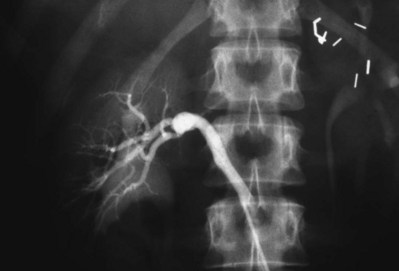

Perimedial (subadventitial) fibroplasia accounts for 10% to 15% of fibrous lesions and is limited to the renal arteries. Angiographically the appearance is similar to that of medial fibroplasia but there are no microaneurysms and extensive collateral circulation is present (Fig. 54–44). Without intervention this entity leads to severe stenosis and progressive obstruction with ischemic nephropathy. The disease often afflicts young females.

Figure 54–44 Selective right renal angiogram demonstrating perimedial (subadventitial) fibroplasia with decent collateral vasculature.